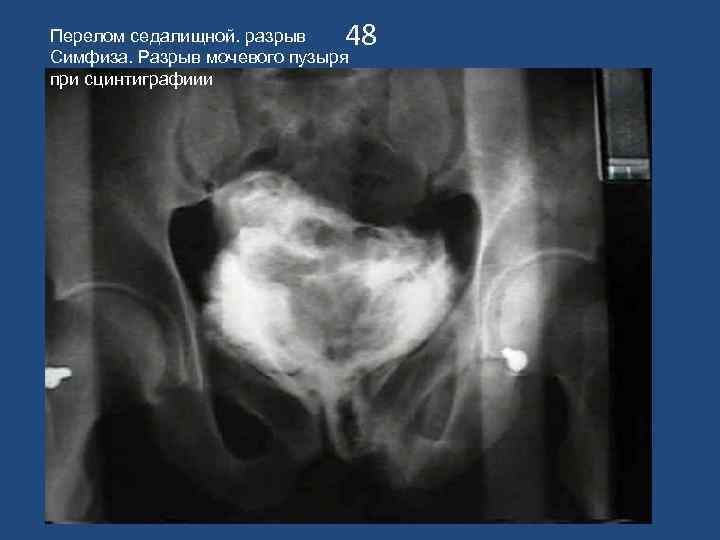

48 Перелом седалищной. разрыв Симфиза. Разрыв мочевого пузыря при сцинтиграфиии